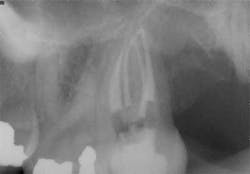

While mandibular incisors are my least favorite teeth to treat, the premolar teeth also provide significant reason for concern as they have highly variable anatomy. The maxillary first and second premolars will have one, two, or three roots and canals. (Figure 3) Maxillary premolar teeth have the smallest mean apical dimension at the apex (11) and the most variable anatomy, with exception of third molars. (12,17) The roots are often very thin, and a bulbous clinical crown may have significant taper to a thin root in the mesial-distal dimension that is broad in the facial-lingual dimension. It is not uncommon to see mesial-distal fractures in maxillary first or second premolars. Maxillary second premolars may have more curvature in the apical portion of the root when the sinus is close to the root ends. (Figure 4)

following root canal treatment in teeth Nos. 4 and 5. An angled

radiograph indicated a high probability for an untreated canal in

tooth No. 4 and as a result, this tooth was retreated.

increased concern about the anatomy in tooth No. 5. This tooth

was subsequently retreated due to persistent symptoms.

were present in both Nos. 4 and 5 following the initial root

canal treatment.